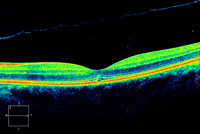

Figura 11. Agujero macular con tracción vítrea.

Figura 12. Agujero macular estadio I.

Figura 16. Agujero macular en estadio IIA.

Figura 17. Agujero macular en estadio IIB, de 208 µm.

Figura 19. Agujero macular en estadio III.

Figura 20. Agujero macular con tracción vítrea.

Figura 21. Agujero macular mediano o de estadio IIB, de 374 µm.

Figura 22. Agujero macular mediano o de estadio IIB, de 326 µm.

Figura 23. Agujero macular de estadio III, de 459 µm.